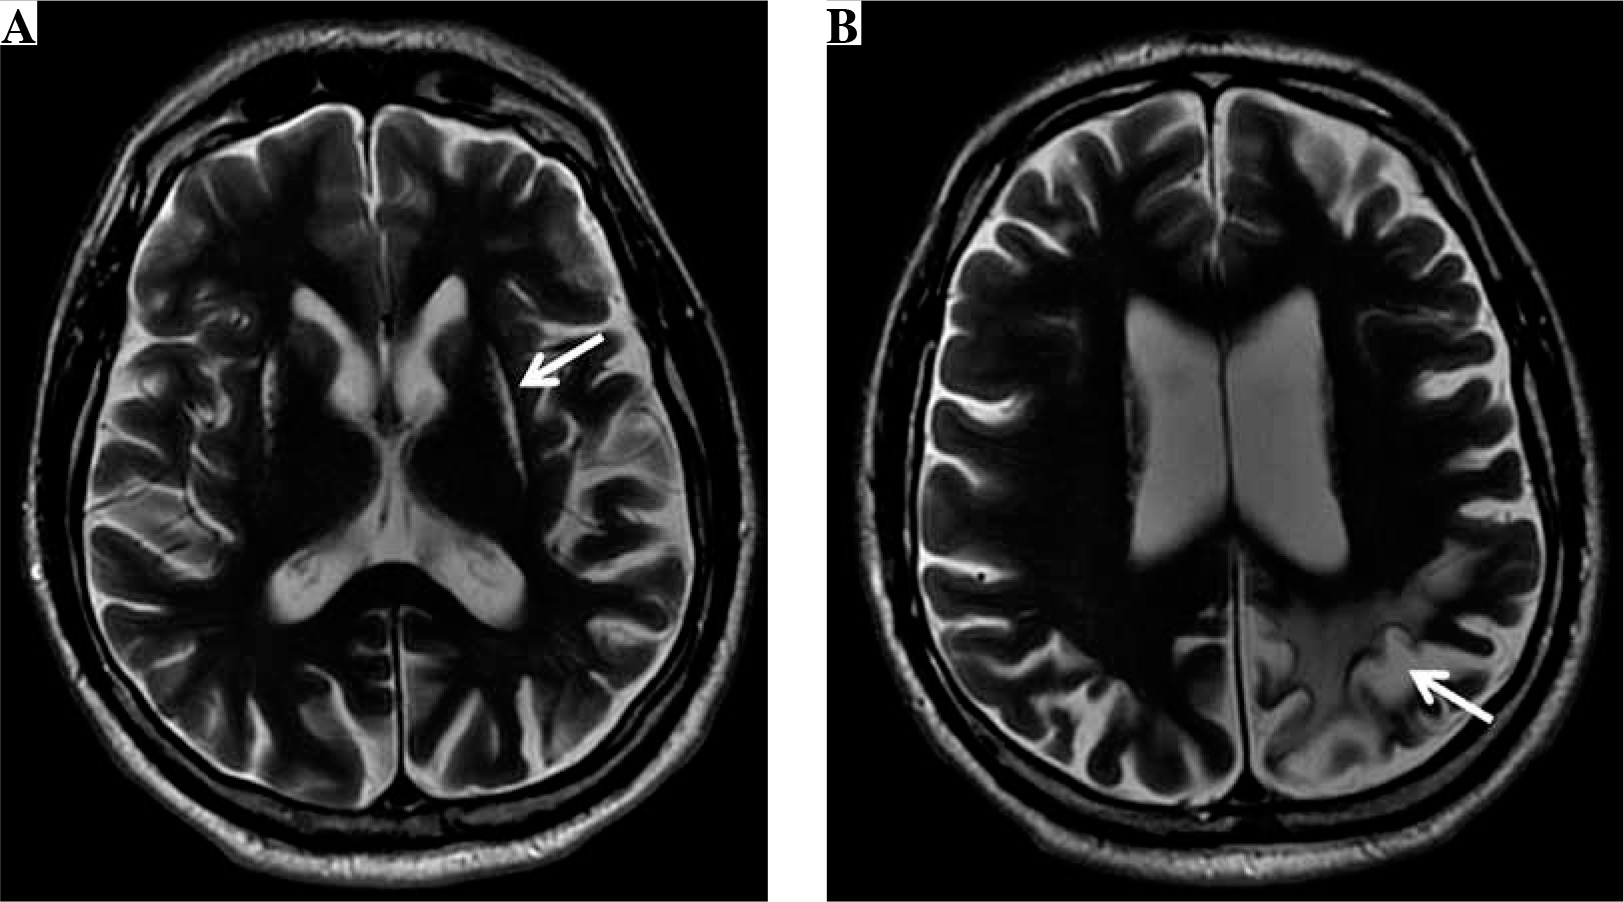

Nine years after the cerebral infarction, features of mild intellectual impairment were still present. The patient had trouble with reading and writing, and showed a slight memory dysfunction. The follow-up neurological examination revealed insignificant right hemiparesis. The brain magnetic resonance (MR) examination (Fig. 1) showed chronic hypoxic-ischemic lesions of the head and the body of the caudate nucleus and putamen bilaterally, further chronic ischemic changes within the cortex and subcortical white matter of the left parietal lobe with segmental cortical atrophy, as well as features of moderate subcortical and cortical atrophy of the brain.

Fig. 1

The brain magnetic resonance (MR) examination, axial T2-weighted images (A, B) show chronic hypoxic-ischemic lesions (arrow) of the head and the body of the caudate nucleus and putamen bilaterally (A), as well as chronic ischemic changes (arrow) within the cortex and subcortical white matter of the left parietal lobe with segmental cortical atrophy (B) as well as features of moderate subcortical and cortical atrophy of the brain